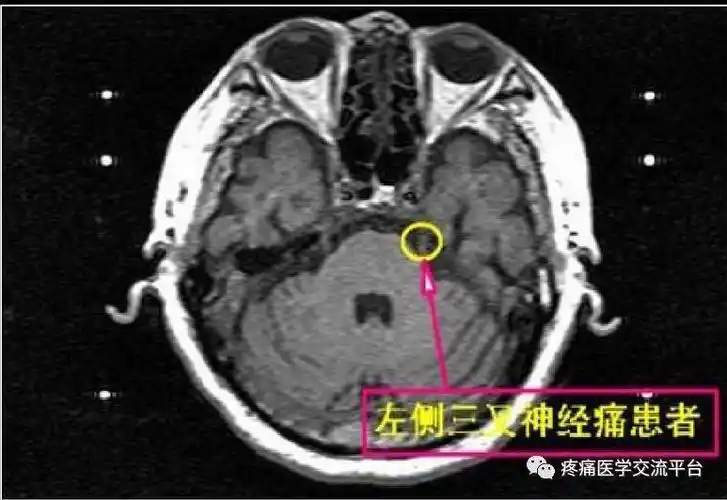

三叉神经解剖及mr表现